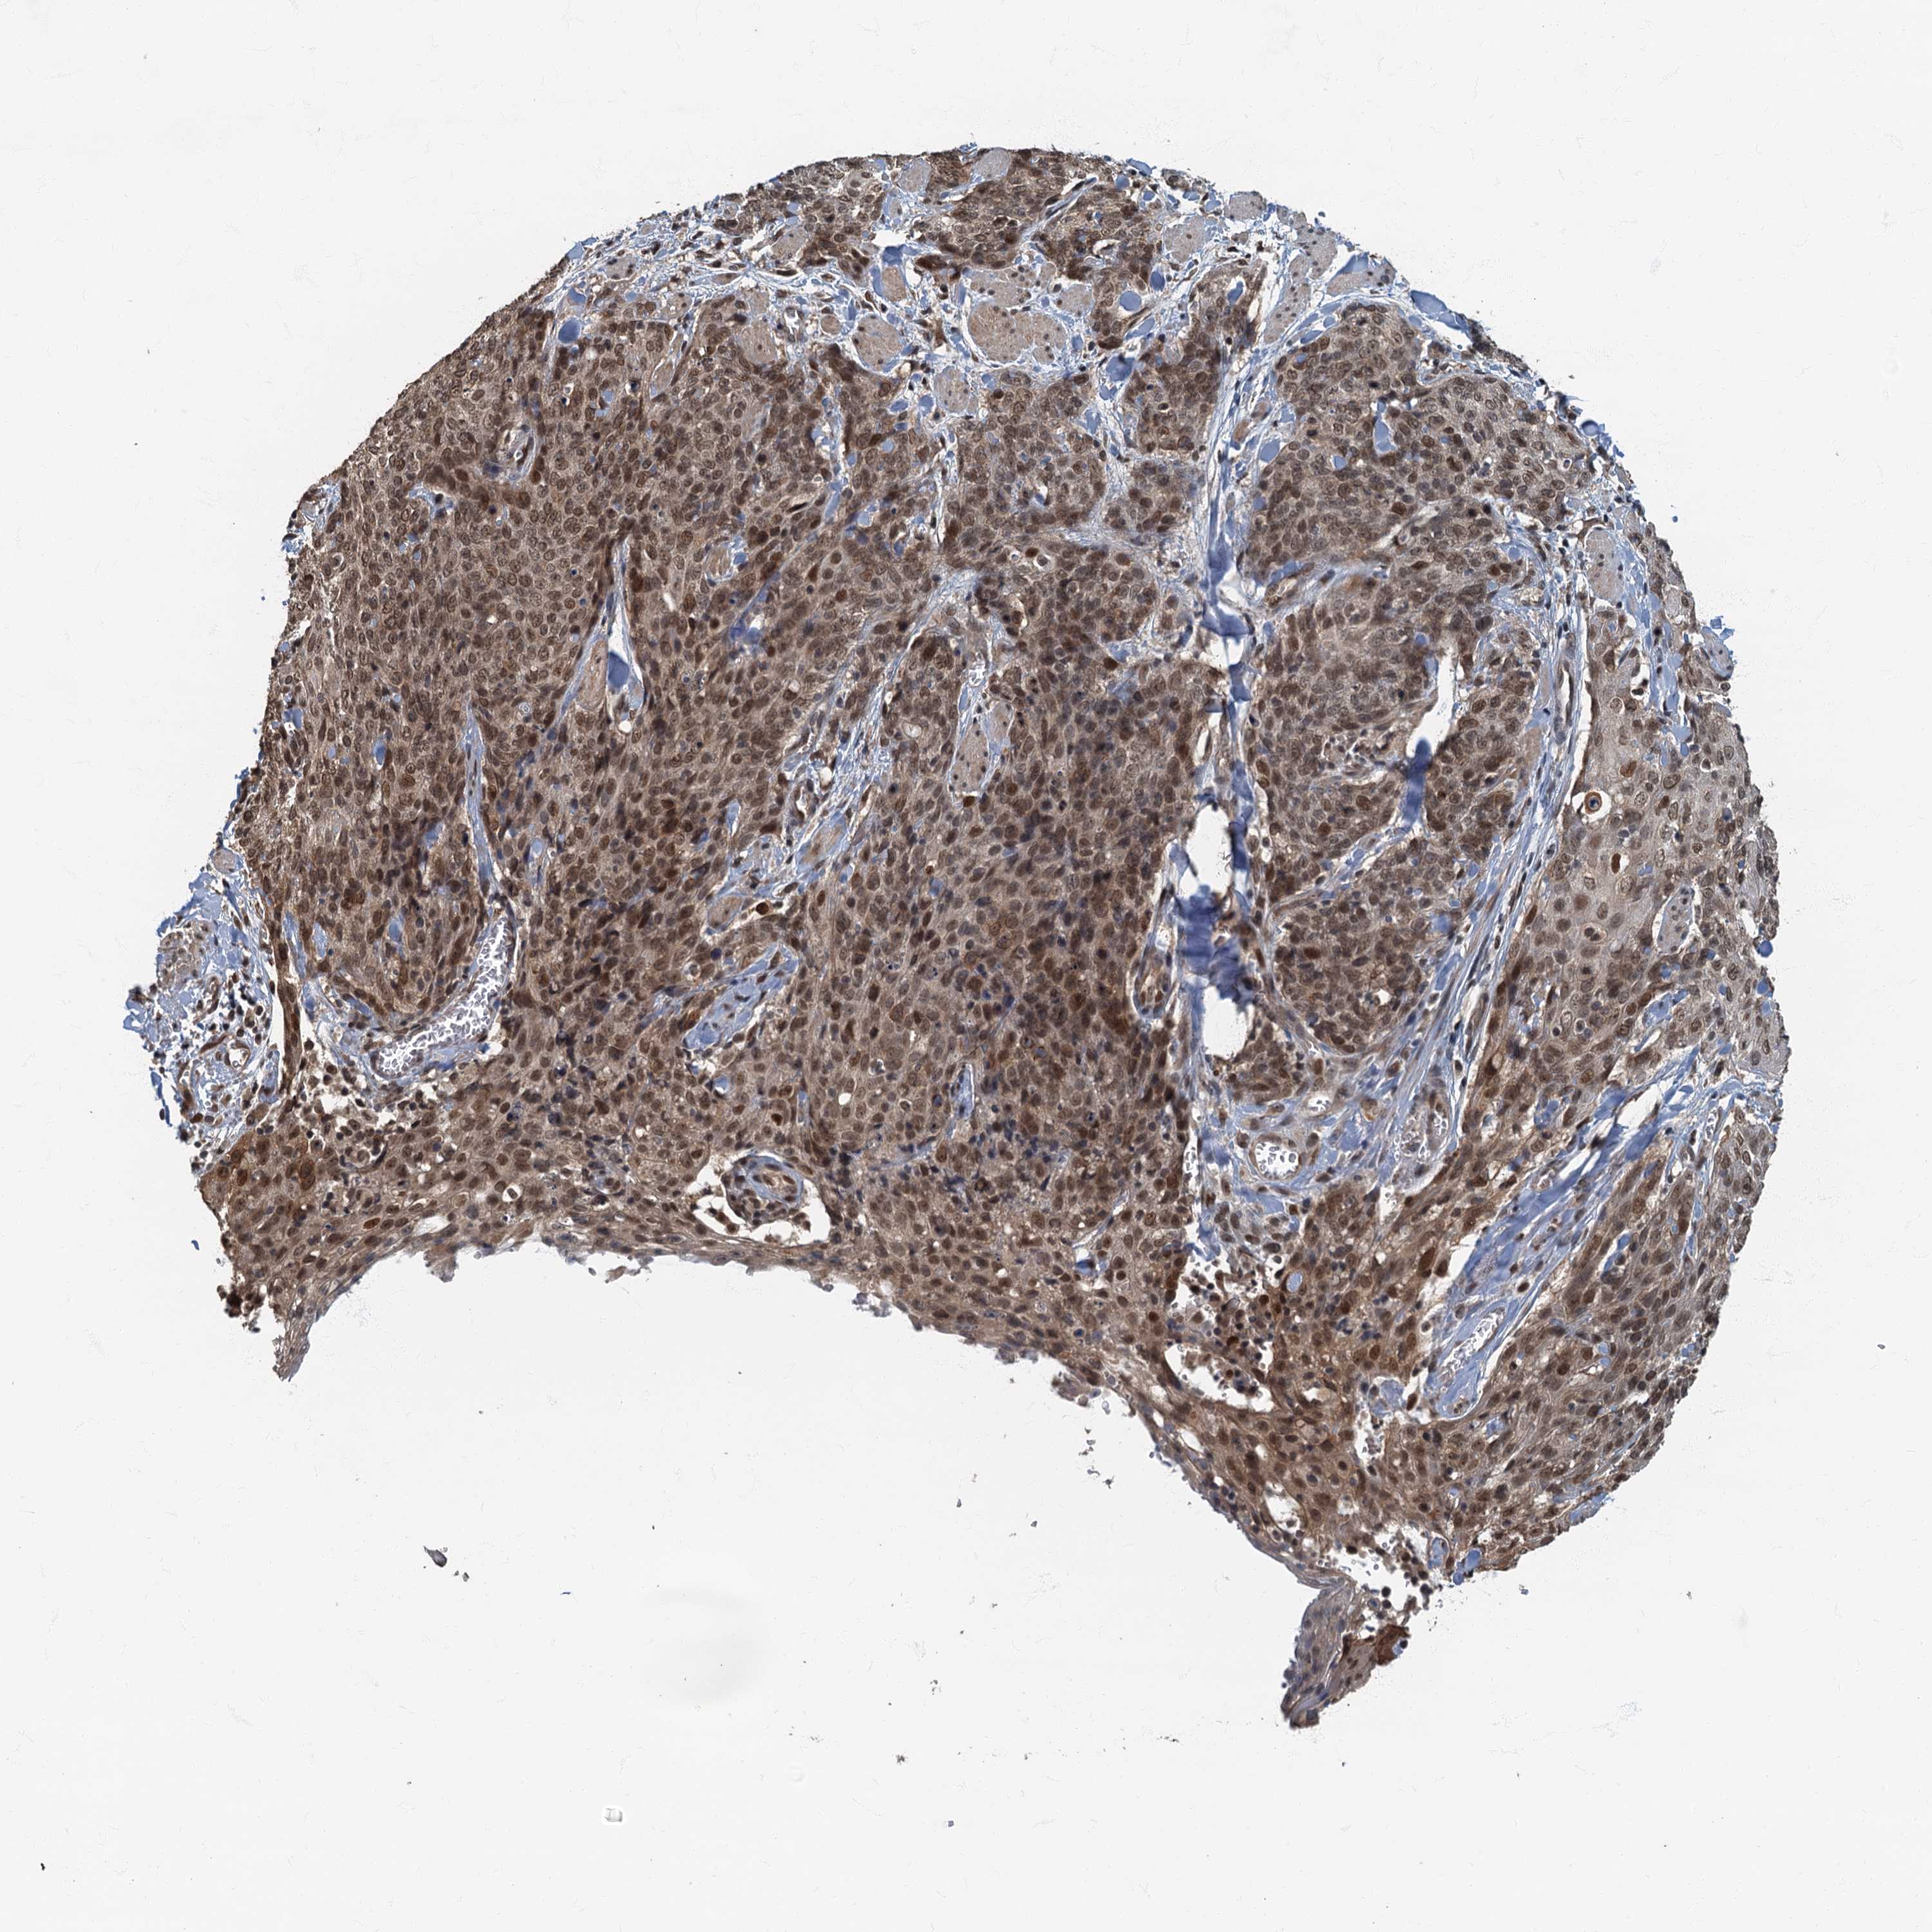

SKIN CANCER - Protein expressioni

A mouse-over function shows sample information and annotation data. Click on an image to view it in a full screen mode. Samples can be filtered based on level of antibody staining by selecting one or several of the following categories: high, medium, low and not detected. The assay and annotation is described here.

Antibody stainingi

Antibody staining in the annotated cell types in the current human tissue is reported as not detected, low, medium, or high, based on conventional immunohistochemistry profiling in selected tissues. This score is based on the combination of the staining intensity and fraction of stained cells.

Each image is clickable and will lead to virtual microscopy that enables deeper exploration of all samples and also displays staining intensity scores, fraction scores and subcellular localization as well as patient and tissue information for each sample.

Antibody HPA039407

Antibody HPA040057

Staining

High

Medium

Low

Not detected

Intensity

Strong

Moderate

Weak

Negative

Quantity

>75%

75%-25%

<25%

None

Location

Nuclear

Cytoplasmic/membranous

Cytoplasmic/membranous,nuclear

Squamous cell carcinoma, NOS